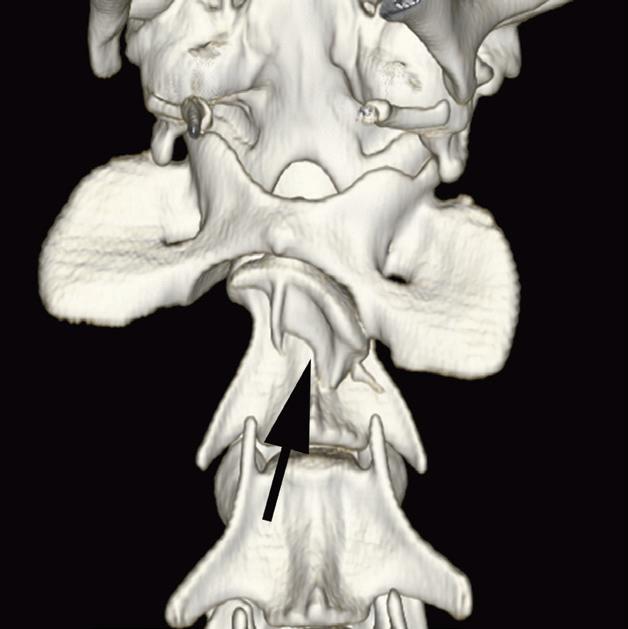

Badanie wykonano u 5-letniego, kastrowanego kota rasy europejskiej po urazie o nieznanej przyczynie, do którego doszło w ciągu 48 godzin poprzedzających badanie. U kota stwierdzono liczne złamania czaszki typowe dla urazów o dużej sile. Prezentowane obrazy ułożono w kolejności od donosowej do doogonowej. Urazy obejmują: złamanie lub zwichnięcie w obrębie kości nosowych i szczękowych (a – strzałka), separacje spojenia żuchwy (b – strzałka), złamania wyrostków pionowych kości podniebiennych (c – strzałki), rozejście spojenia podniebiennego (c – grot strzałki), złamania kości skrzydłowych (d – strzałki), doogonowe zwichnięcie prawego wyrostka kłykciowego (e – grot strzałki) oraz złamanie przez wyrostek jarzmowy lewej kości skroniowej (e – strzałka)